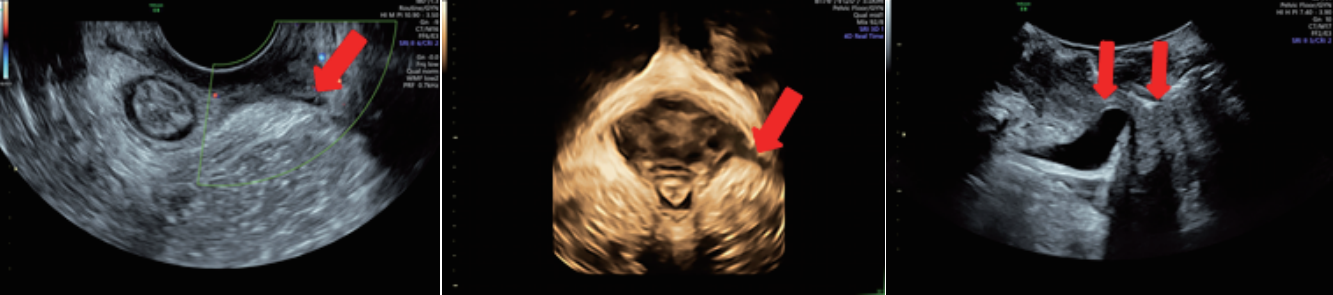

廣泛應(yīng)用于婦產(chǎn)超聲臨床領(lǐng)域,尤其在產(chǎn)科、不孕不育生殖醫(yī)學(xué)和女性盆底功能障礙性疾病等領(lǐng)域,提供高品質(zhì)圖像及專業(yè)的婦產(chǎn)超聲臨床解決方案。

案例圖

女性產(chǎn)后盆底功能檢查

輸卵管